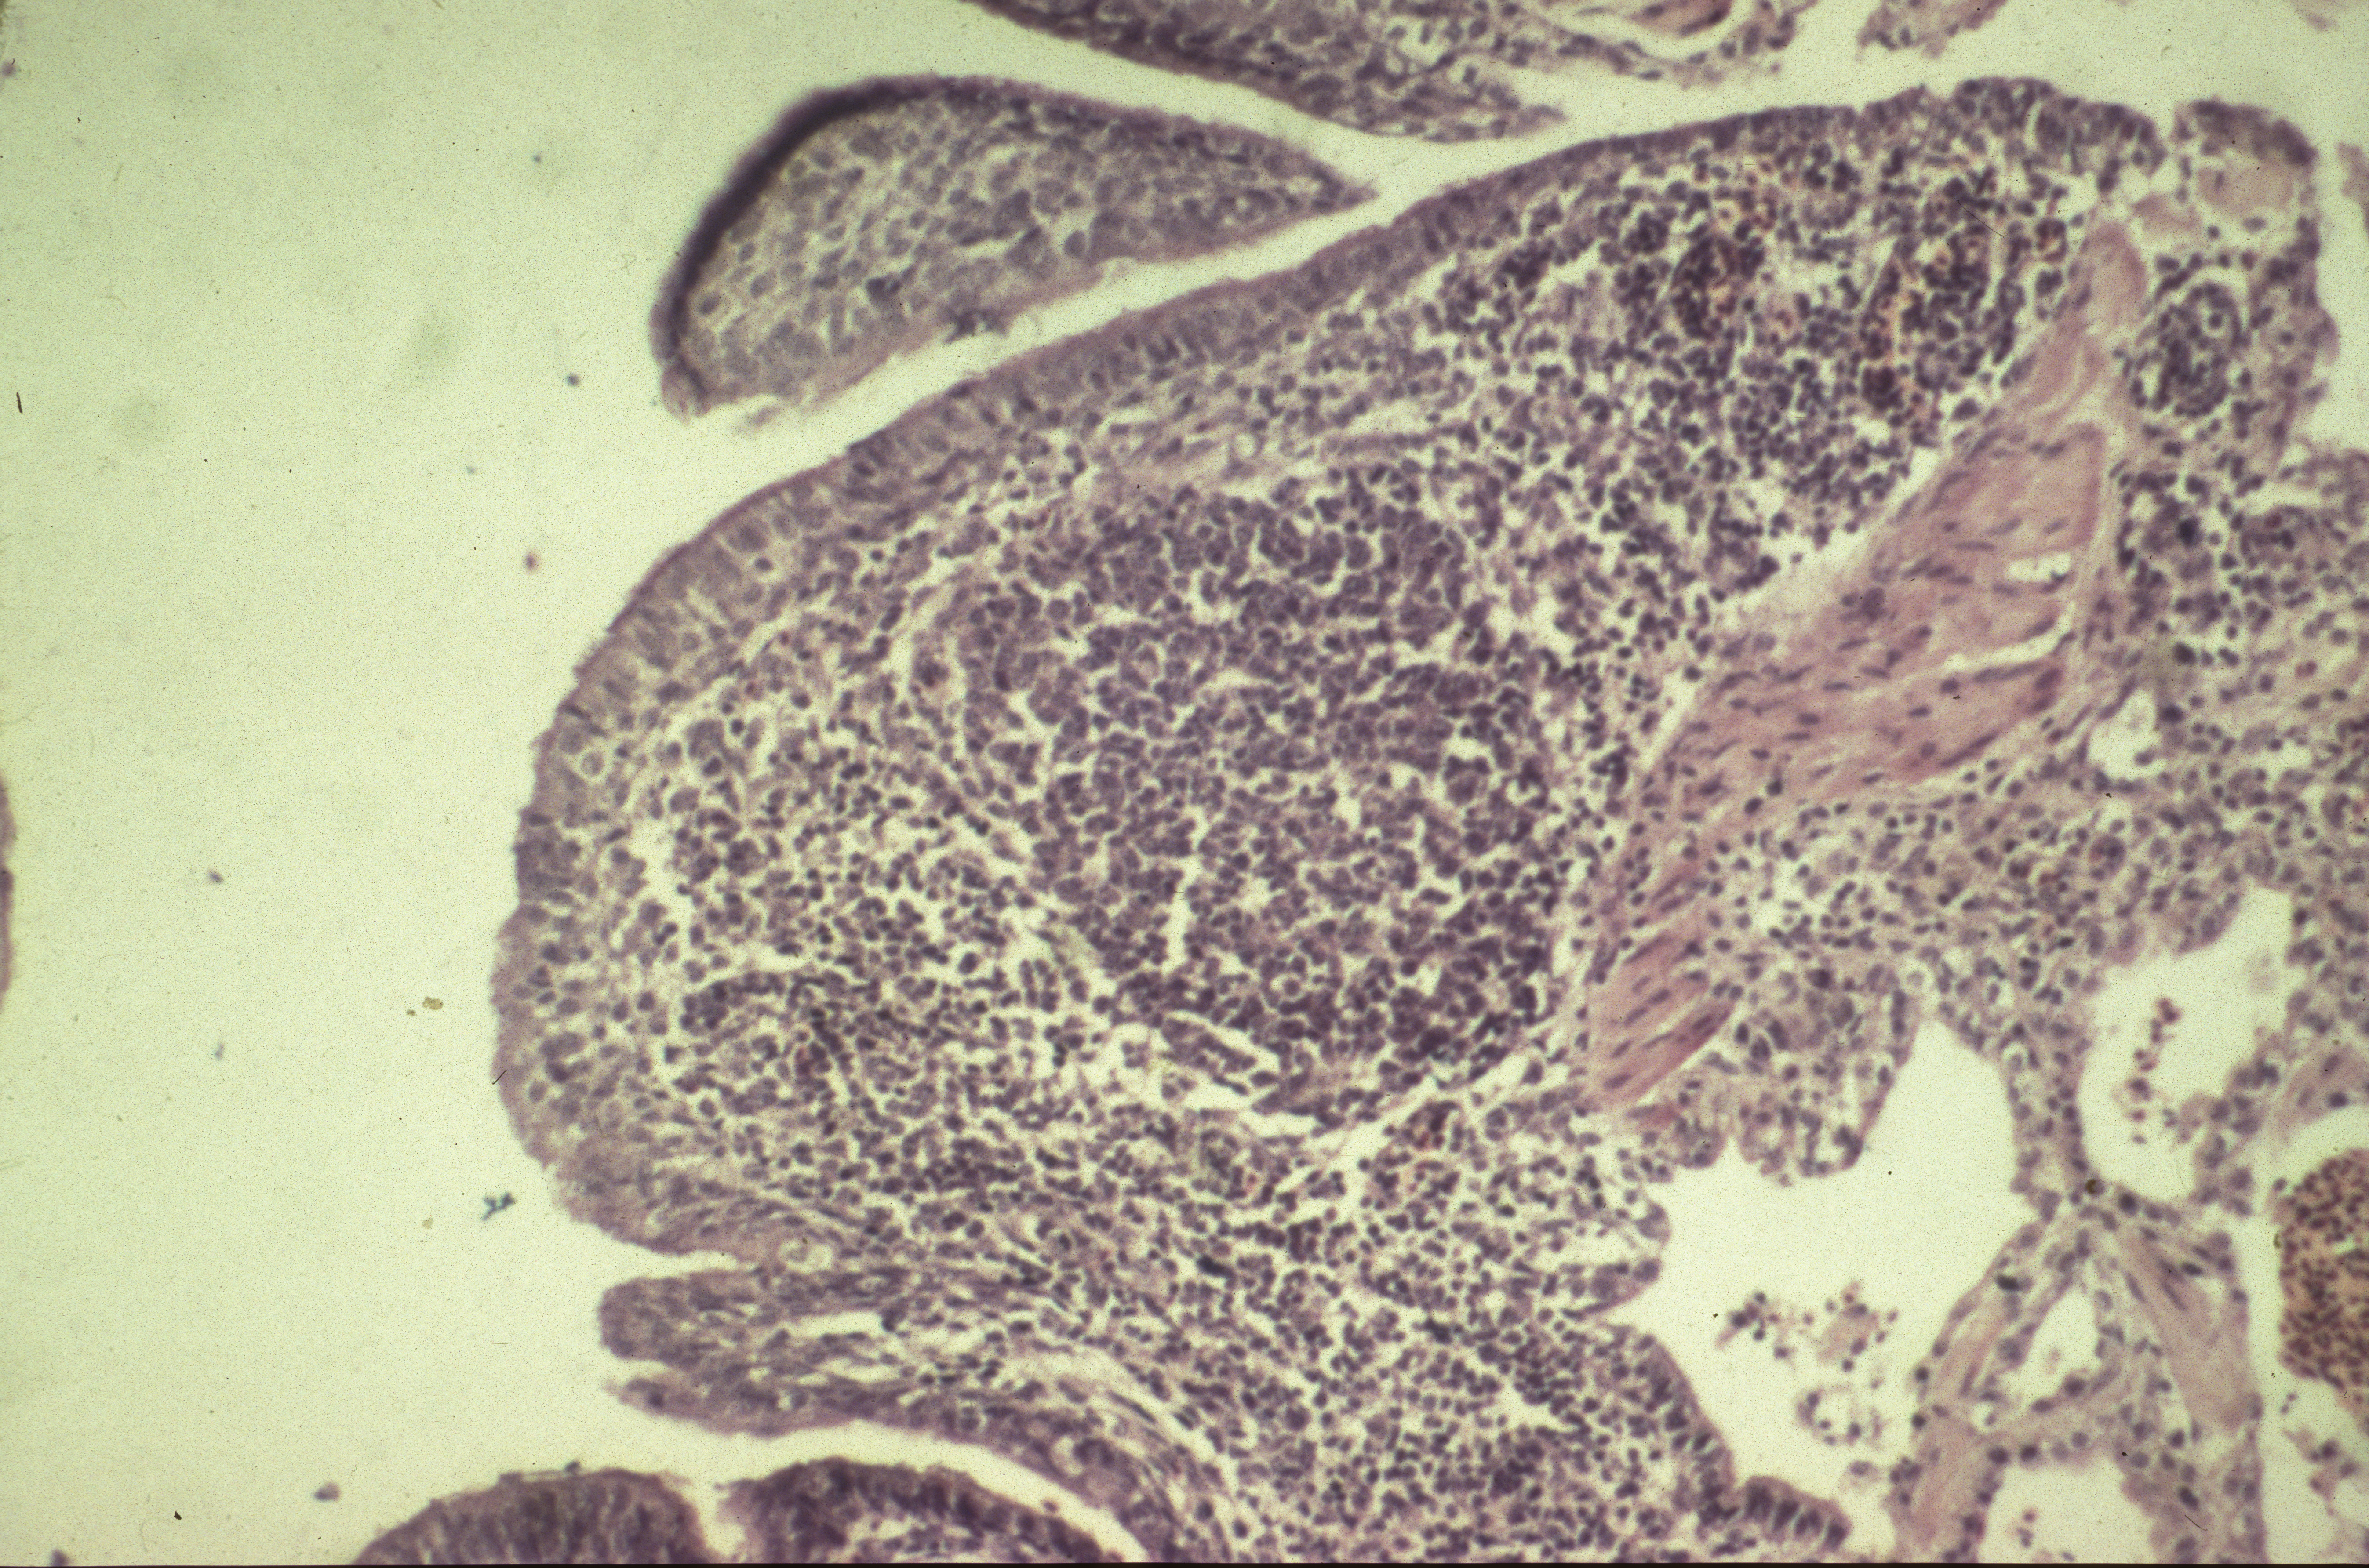

Mycoplasma synoviae infection (slide study set no. 12) Item Info

Mycoplasma synoviae infection (slide study set no. 12)

Slide study set #12, mycoplasma synoviae infection, 2 sets (includes 40 color slides), 1983